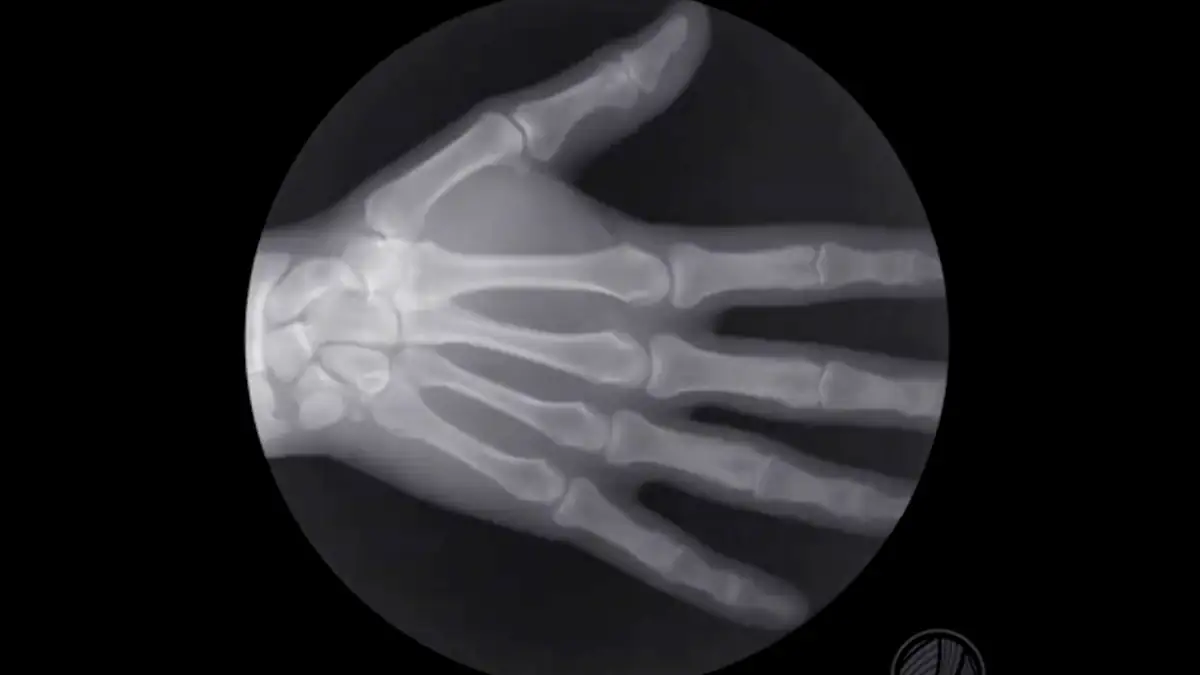

Zumindest darauf scheint die Antwort eindeutiger zu sein. Denn wie die Expertin erklärt, gebe es bisher keinerlei Hinweise darauf, dass durch Fingerknacken langfristige Gelenk- oder anderweitige Schäden verursacht würden. Sie berichtet von einem Arzt aus Kalifornien, der dazu ein bemerkenswertes Selbstexperiment über 50 Jahre durchführte. Dabei ließ er jeden Tag zweimal die Gelenke an seiner linken Hand knacken, die an der rechten nicht. Spätere Röntgenaufnahmen zeigten jedoch in keiner seiner Hände eine Arthritis.